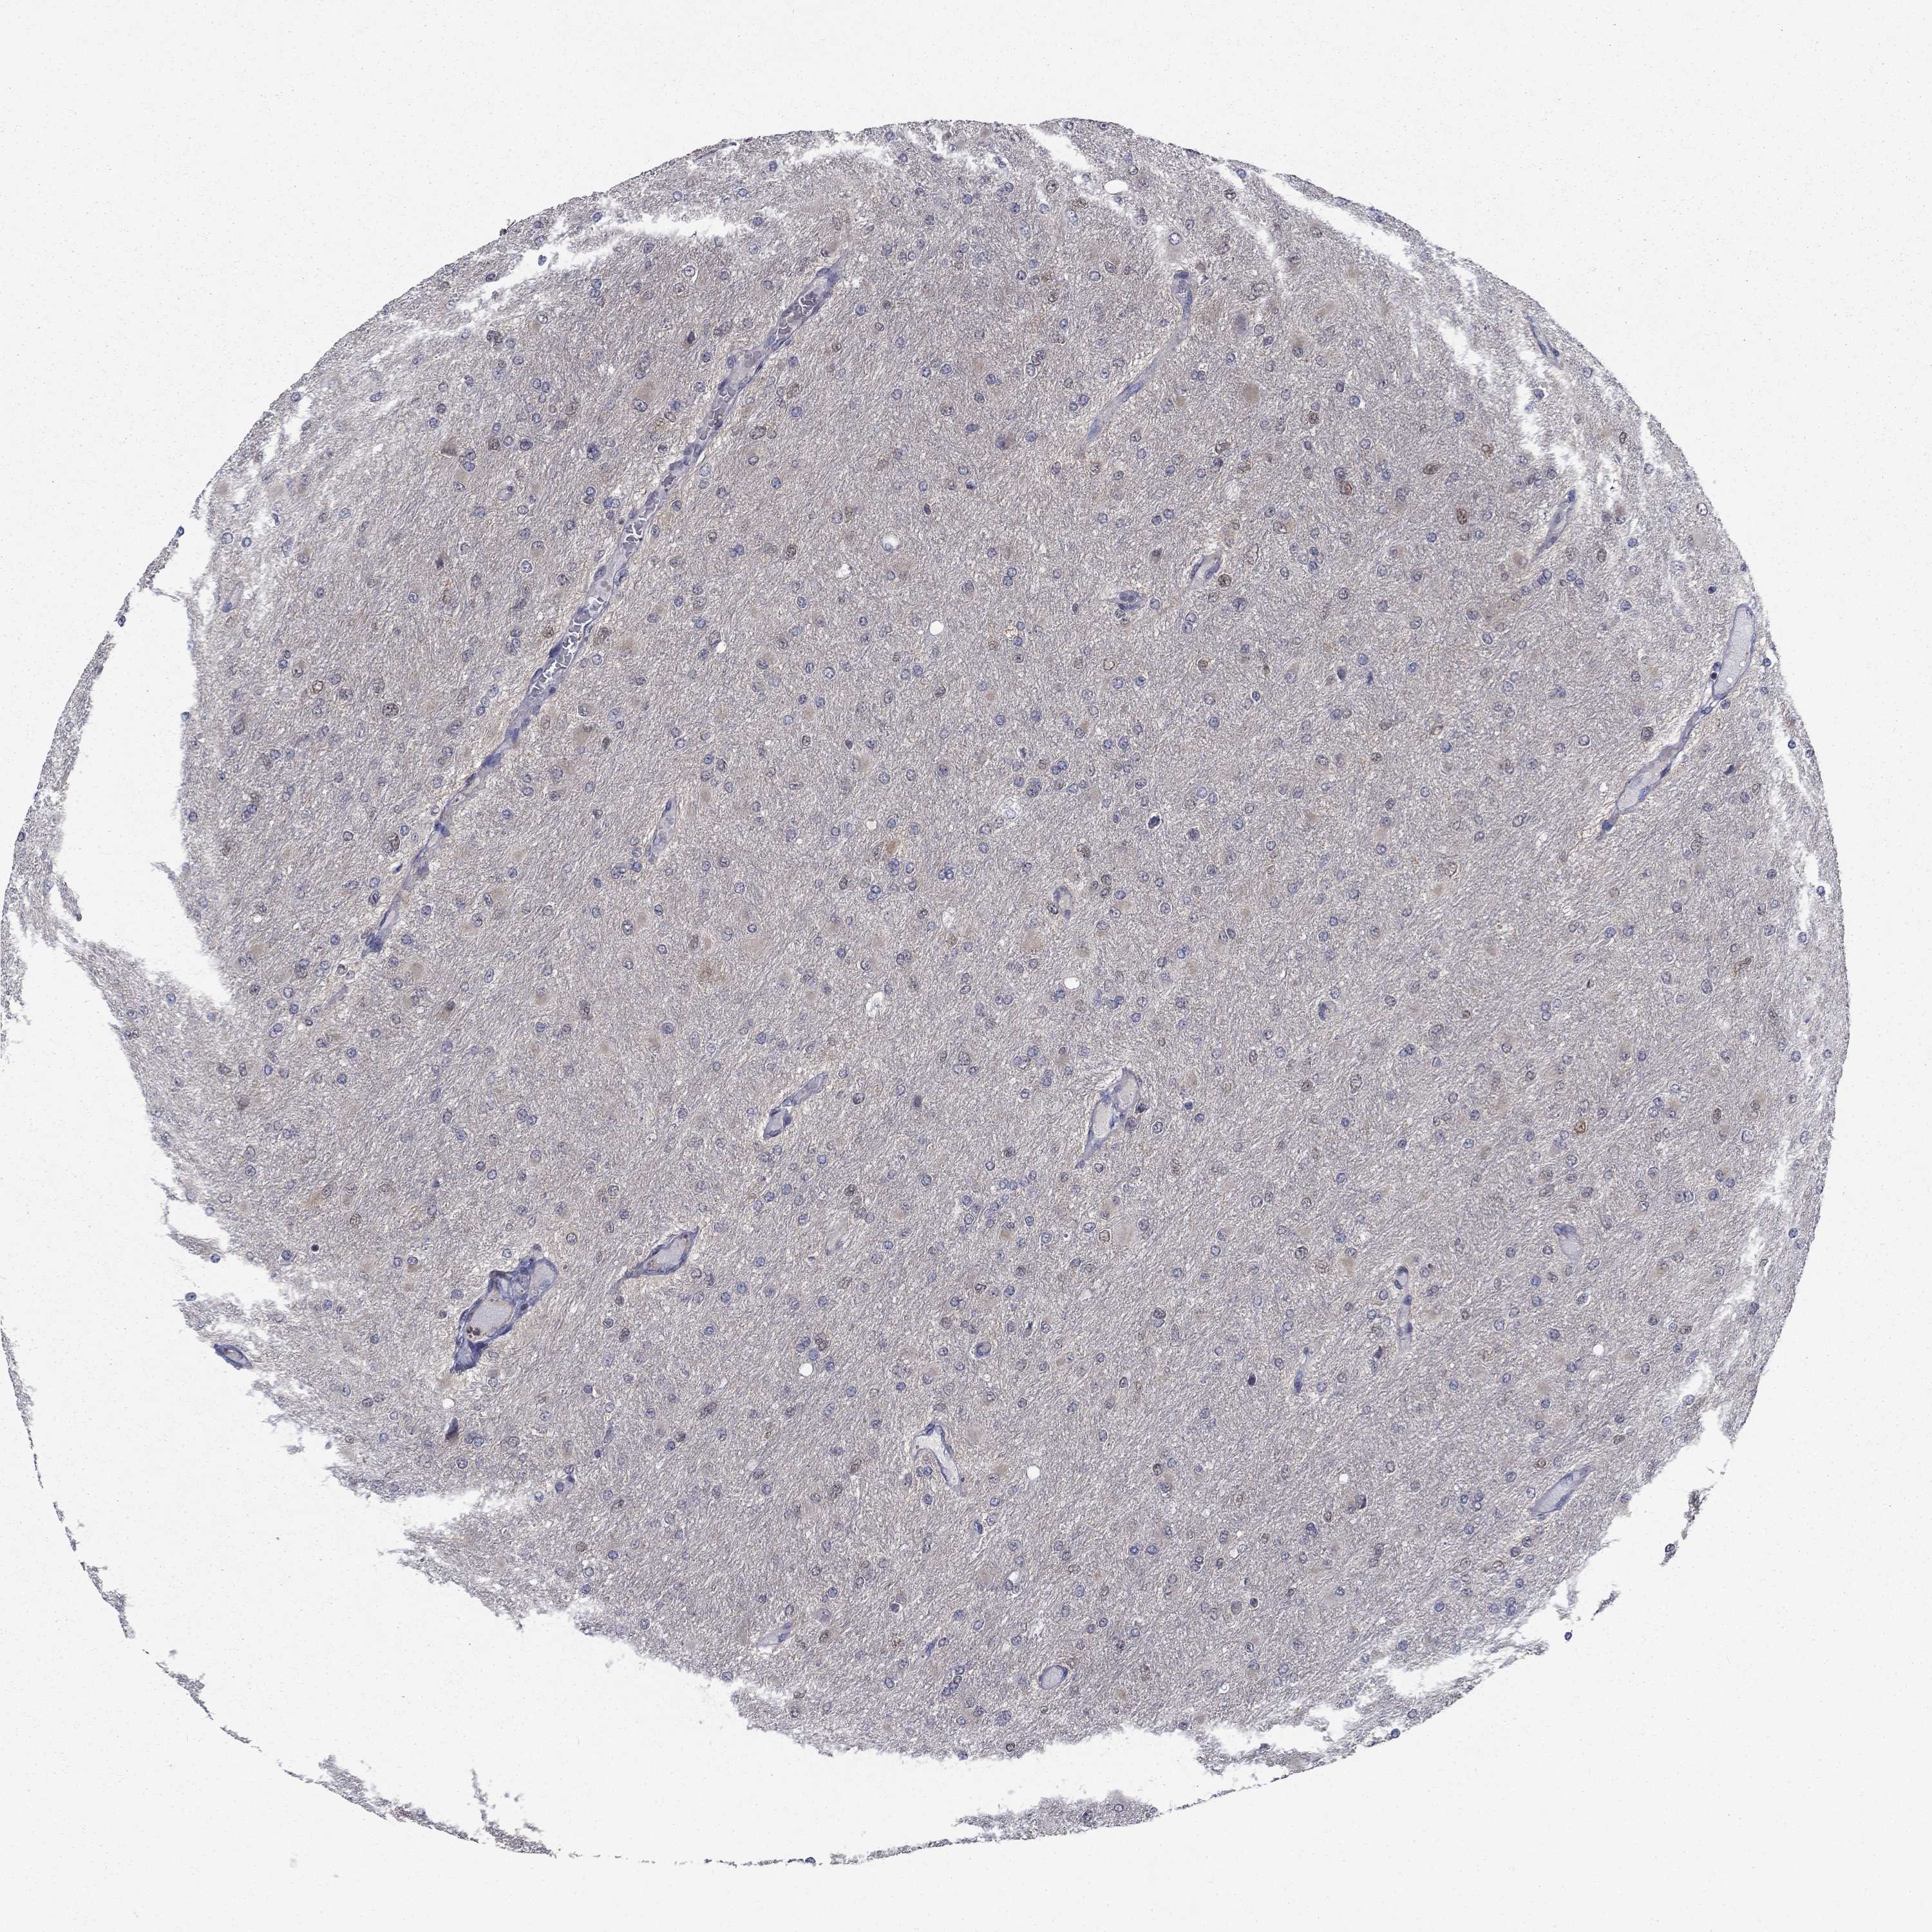

GLIOMA - Protein expressioni

A mouse-over function shows sample information and annotation data. Click on an image to view it in a full screen mode. Samples can be filtered based on level of antibody staining by selecting one or several of the following categories: high, medium, low and not detected. The assay and annotation is described here.

Note that samples used for immunohistochemistry by the Human Protein Atlas do not correspond to samples in the TCGA dataset.

Antibody stainingi

Antibody staining in the annotated cell types in the current human tissue is reported as not detected, low, medium, or high, based on conventional immunohistochemistry profiling in selected tissues. This score is based on the combination of the staining intensity and fraction of stained cells.

Each image is clickable and will lead to virtual microscopy that enables deeper exploration of all samples and also displays staining intensity scores, fraction scores and subcellular localization as well as patient and tissue information for each sample.

Antibody HPA036999

Antibody HPA041289

Staining

High

Medium

Low

Not detected

Intensity

Strong

Moderate

Weak

Negative

Quantity

>75%

75%-25%

<25%

None

Location

Nuclear

Cytoplasmic/membranous

Cytoplasmic/membranous,nuclear

Glioma, malignant, High grade

Glioma, malignant, Low grade